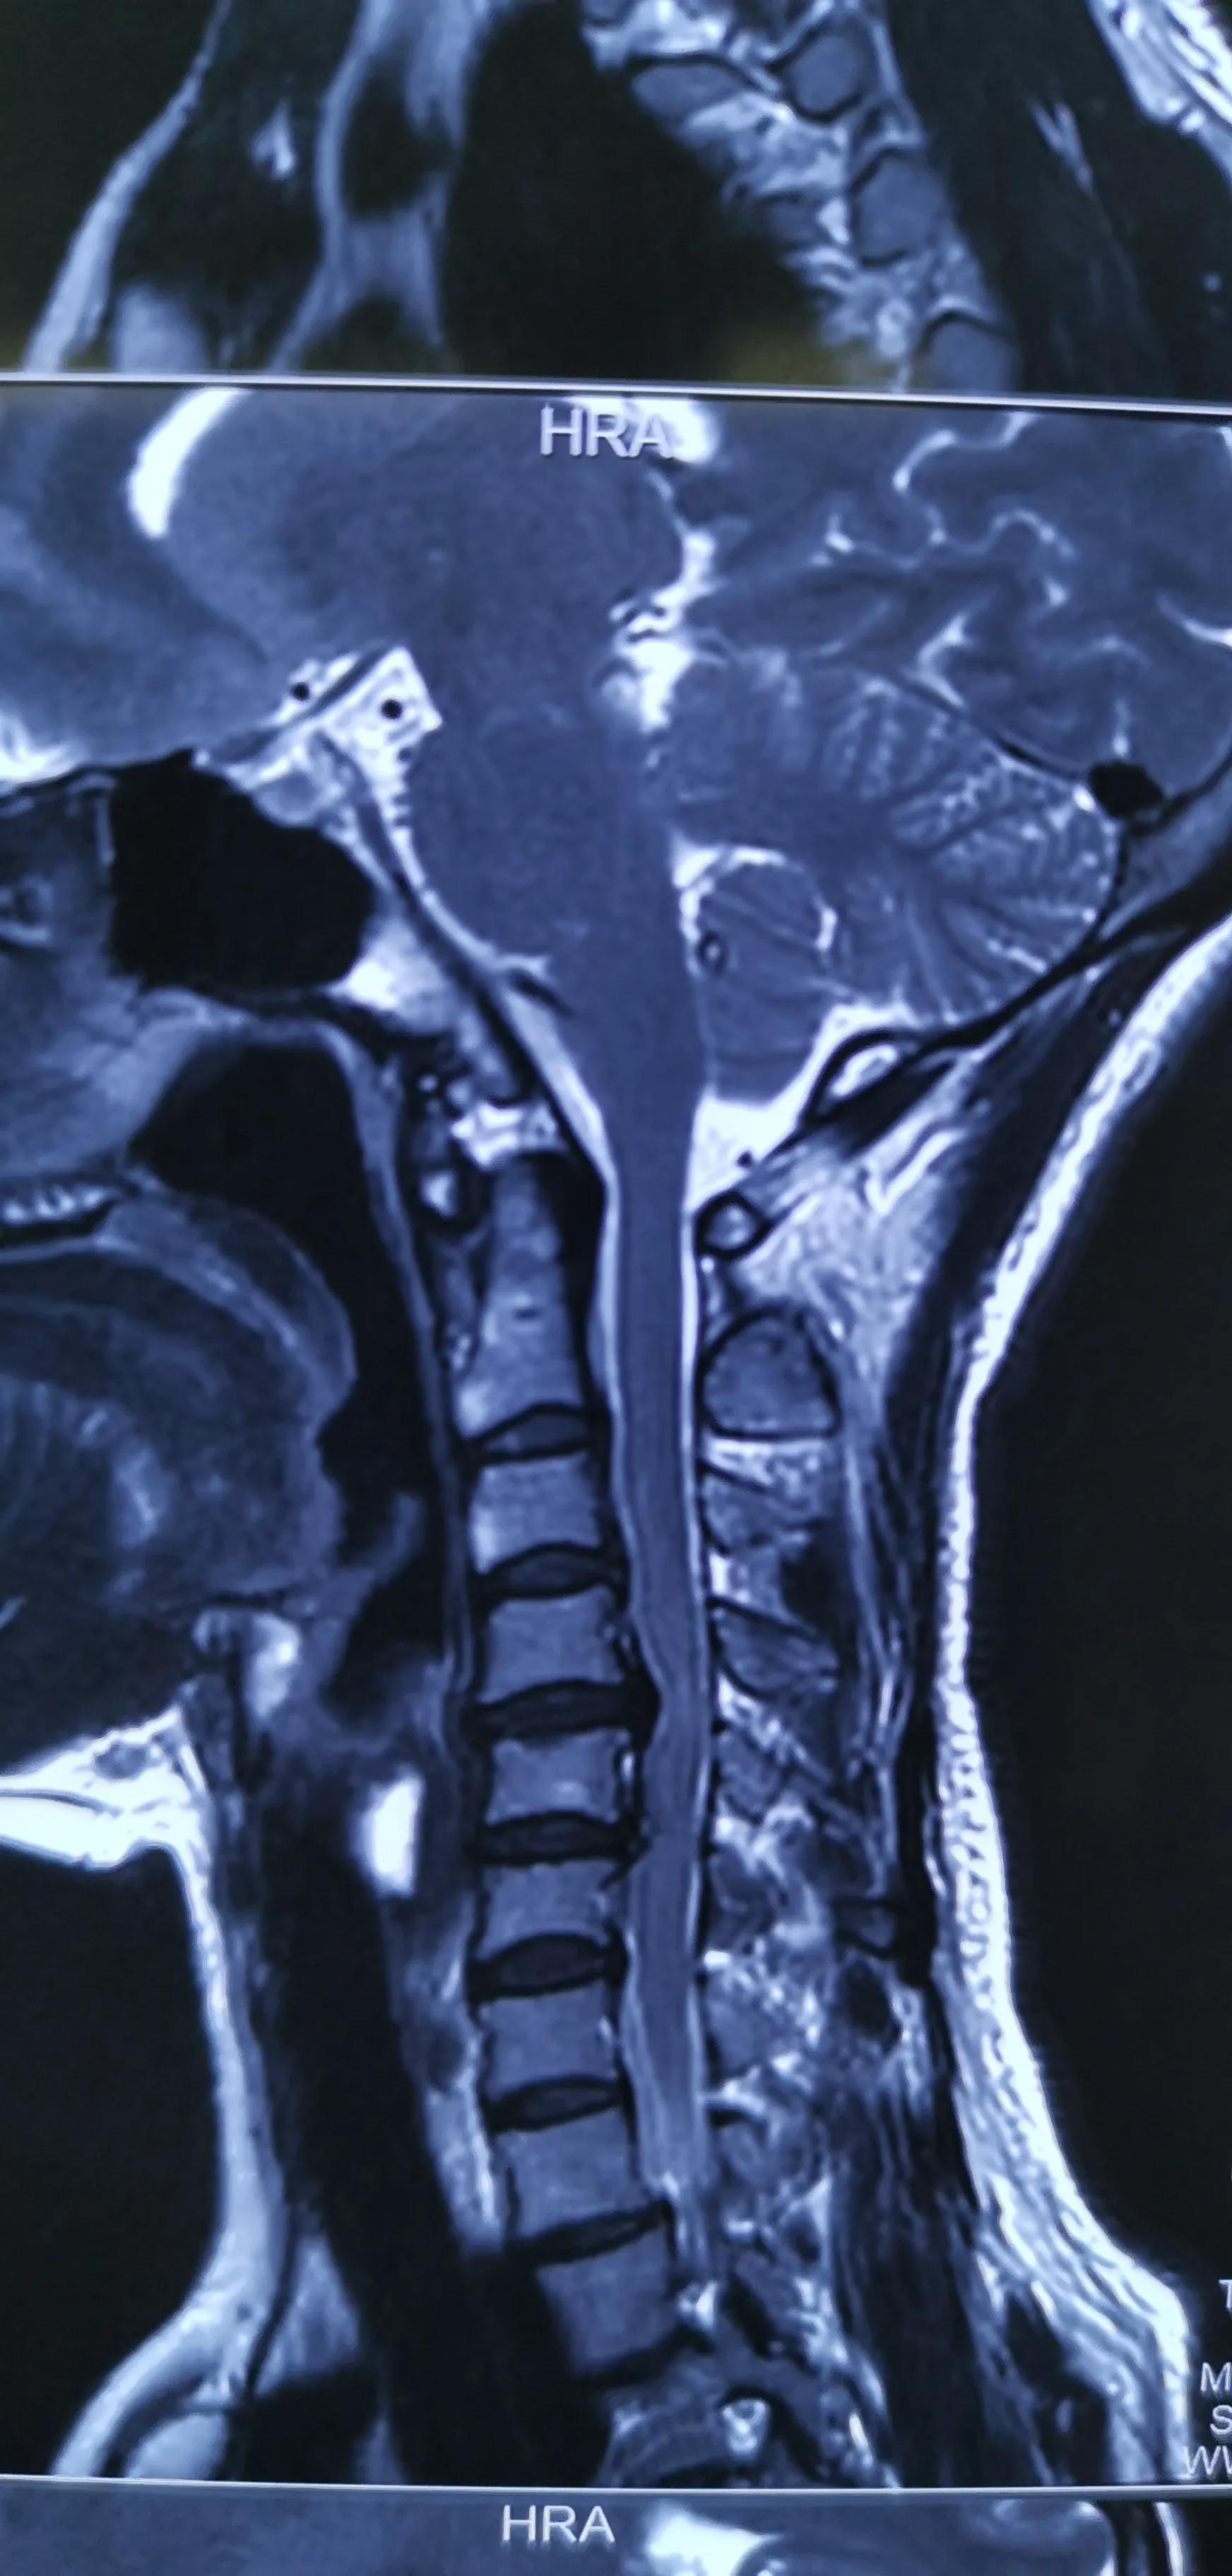

43岁女性,颈肩部疼痛严重伴左侧上肢放射痛无力,mri提示C4/5,C5/6椎间盘突出,CT提示钙化。予前路C5椎体次全切除,椎间盘摘除,椎间钛笼植骨融合钢板内固定,术后疼痛基本消失,肌力逐渐恢复,麻木缓解。

对这类椎间盘突出钙化的患者如果疼痛严重或伴肌力下降或行走不稳,提示压迫神经或脊髓,不宜推拿,可手术减压,效果显著。